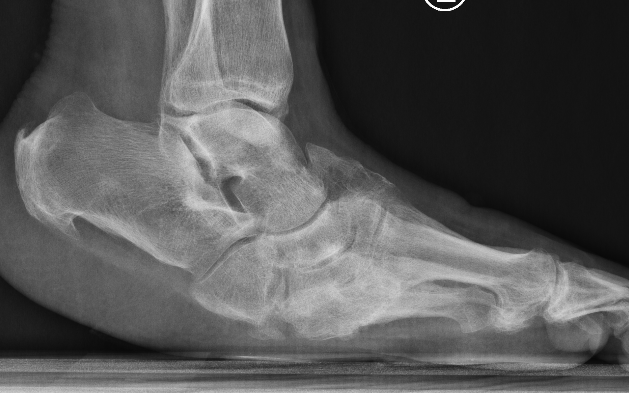

Xray

Midfoot collapse

Midfoot collapse and rocker bottom foot with small ulcer

Midfoot collapse with subluxation of midtarsal joints

Hindfoot collapse with ulcer